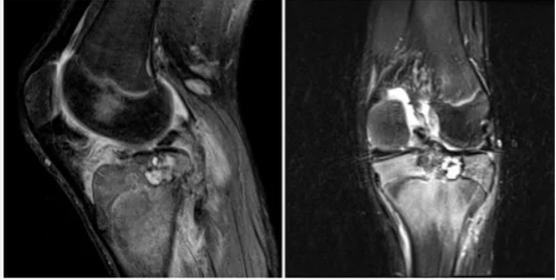

外院行经腘窝肿瘤刮除术,术后影像下显示:

X线片较术前未见明显改变,胫骨近端骨骺区不均匀透亮影,累及生长板。